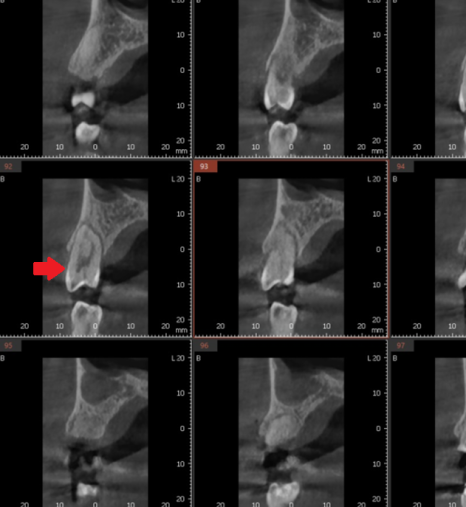

240104 뿌리까지 금이 간 경우

깨진 범위가 넓거나 뿌리까지 금이 간 경우,

결국 발치가 불가피할 수 있습니다.

240104 뿌리까지 치아에 금이가고 부러진 경우

뿌리까지 금이 간 치아는

충치가 없어도 발치 후 임플란트로 이어질 수 있습니다.